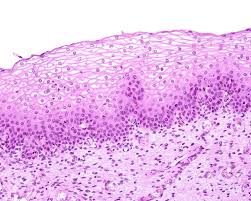

stratified squamous

several layers of cells that are cuboidal & flat; found in the skin surface, mouth, & esophagus; helps with protecting against abrasions